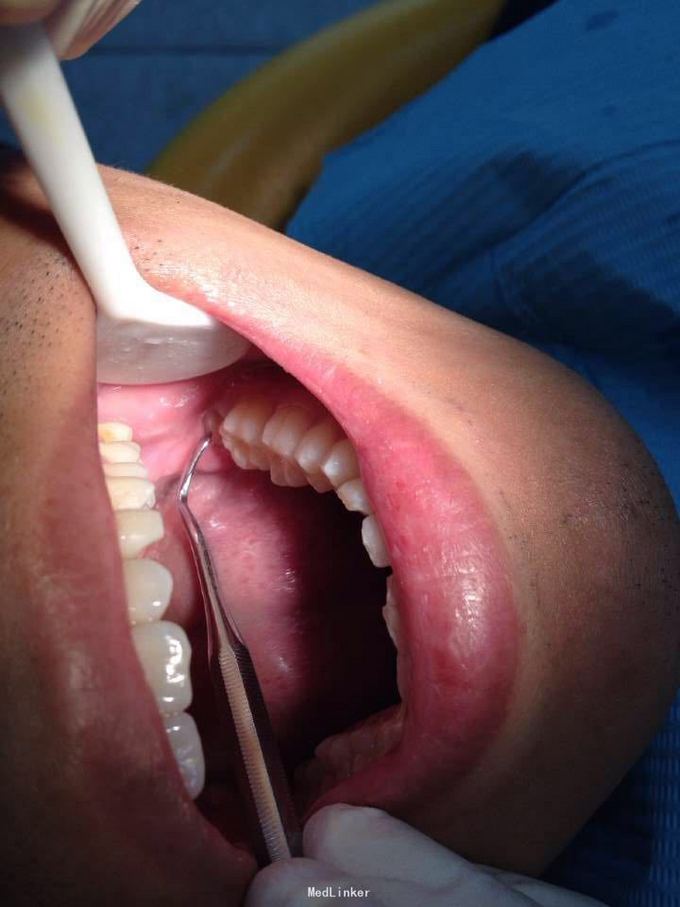

体检时发现左下智齿阻生,要求拔除,想微创一点就没有翻瓣没有去骨,硬是把牙一块一块分开挖出来的,当然了耗时我一个小时,不知道这样对不对,还是直接翻瓣去骨后分分钟敲出来对患者更好